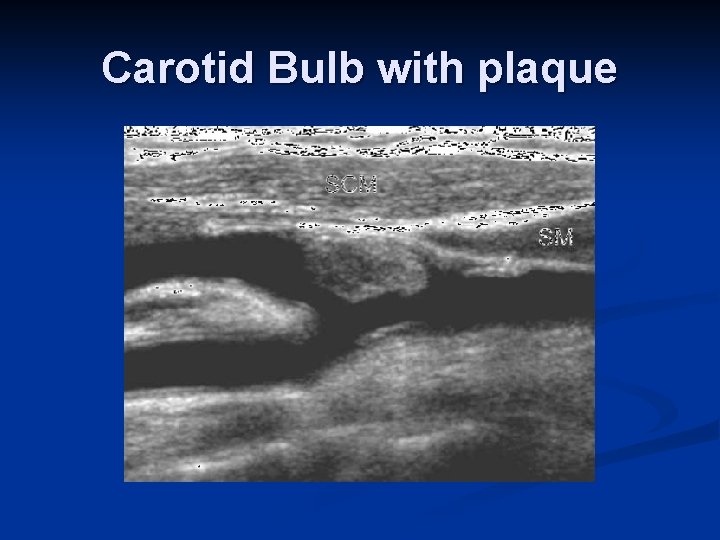

Carotid Bulb with plaque

Carotid Ultrasound Examination Gray Scale Image n Gray-Scale Image n Vessel Wall Thickness n n IM Complex -. 8 mm may be considered abnormal Plaque Characterization n Homogeneous – smooth surface, uniform echogenicity (p 953) Calcified – echogenic with posterior shadowing (p 954) Heterogeneous – complex with at least one sonolucent area corresponding to at least 50% of plaque volume (p 955) n n Interplaque hemorrhage – “Swiss cheese” appearance Plaque ulceration – focal depression/break in surface; or anechoic area that extends to plaque surface; use color/power Doppler (p 952) Some soft plaque may be very difficult to see on US Evaluation of Stenosis – % stenosis by diameter/area – taken in transverse plane (p 957)